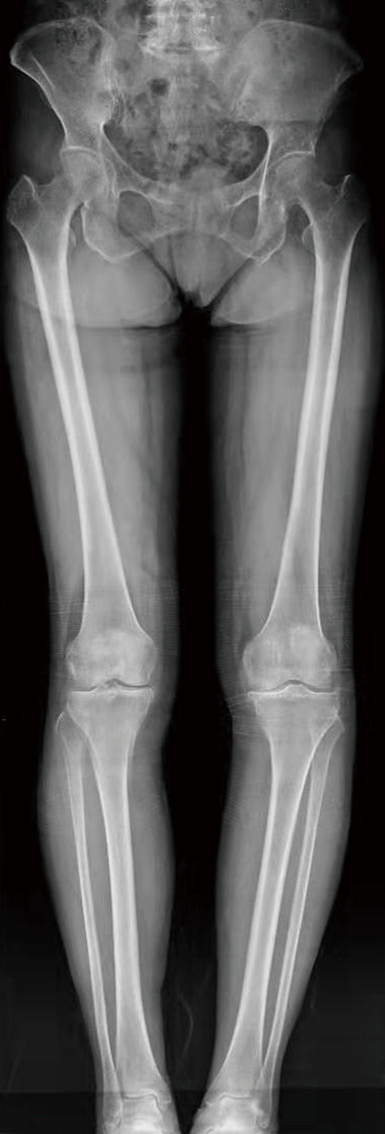

病例4 :使用计算机导航系统对骨性关节炎患者进行全膝关节置换,在术中实时观察假体安装的位置和角度,术后膝关节平衡、稳定,下肢力线得到精准恢复